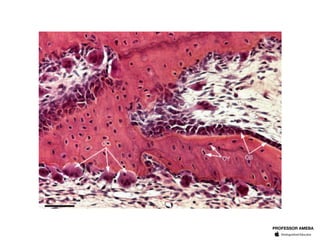

O tecido ósseo é composto por células e matriz extracelular calcificada. Osteócitos situam-se em lacunas na matriz, osteoblastos sintetizam a parte orgânica da matriz, e osteoclastos são células multinucleadas que reabsorvem o tecido ósseo durante a remodelação óssea. A matriz é formada por colágeno orgânico e hidroxiapatita inorgânica.